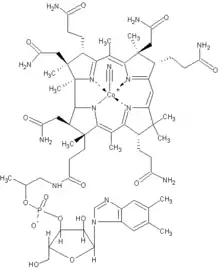

Patients with bacterial overgrowth that is longstanding can develop complications of their illness as a result of malabsorption of nutrients.[9] Laboratory test results may include elevated folate, and, less commonly, vitamin B12 deficiency or other nutritional deficiencies.[4] Anemia may occur from a variety of mechanisms, as many of the nutrients involved in production of red blood cells are absorbed in the affected small bowel. Iron is absorbed in the more proximal parts of the small bowel, the duodenum and jejunum, and patients with malabsorption of iron can develop a microcytic anemia, with small red blood cells. Vitamin B12 is absorbed in the last part of the small bowel, the ileum, and patients who malabsorb vitamin B12 can develop a megaloblastic anemia with large red blood cells.[5]